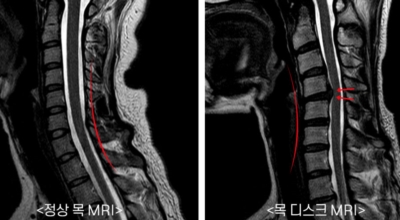

목디스크 증상이 나타날때 빨리 발견하여 비수술 치료를 받고 꾸준히 관리하는 것이 베스트이죠. 목디스크 환자 중 수술을 진행하는 환자는 2% 미만으로 현저히 적다고 해요. 수술을 진행하는 경우는 감각이 느껴지지 않는 마미증후군이나, 한쪽 다리가 눈에 띌 정도로 야윈 경우에만 진행하므로 올바른 자세 교정만으로도 충분히 호전될 수 있는 질병이죠. 목에 연관된 검사는 MRI나 CT를 이용해요. 그러나 전자의 경우 비용이 굉장히 비싸기 때문에 디스크 증세가 확실하다고 생각될 경우에만 선택적으로 하고 의무적으로 하는 건 아니니까 비용에 대해선 부담을 가지지 마시길 바래요.